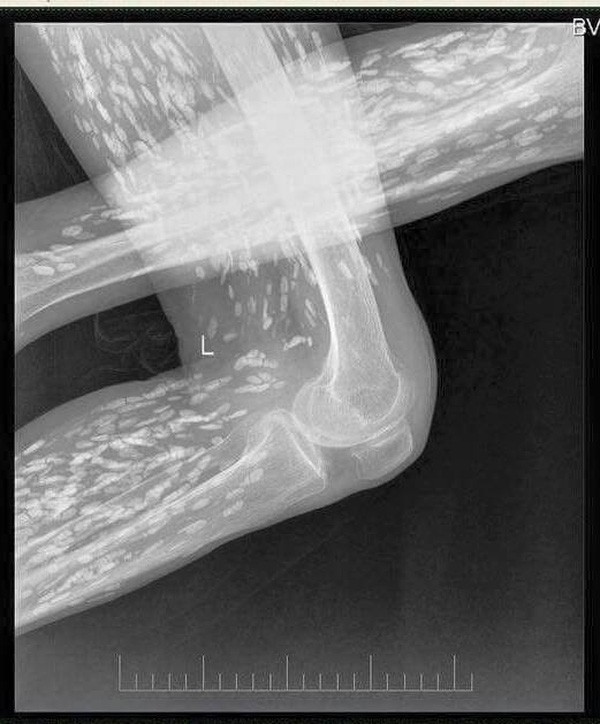

Tuy nhiên, do bệnh tình đã bước sang giai đoạn nghiêm trọng nên người đàn ông tiếp tục được chuyển tới Bệnh viện Nhân dân số 8 ở Quảng Châu để điều trị. Kết quả chụp X-quang cho thấy, những đốm trắng nhỏ xuất hiện lấm chấm khắp cơ thể chính là sán.